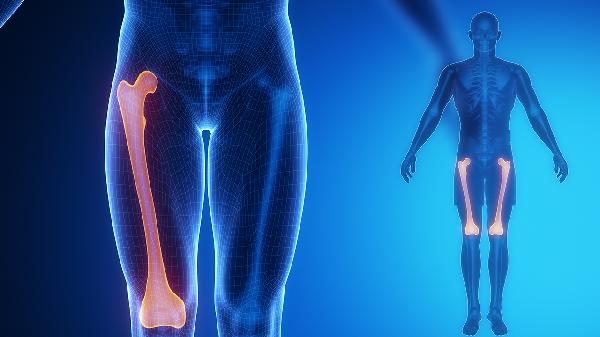

骨折二次复位的最佳时间

骨折后复位的最佳时间